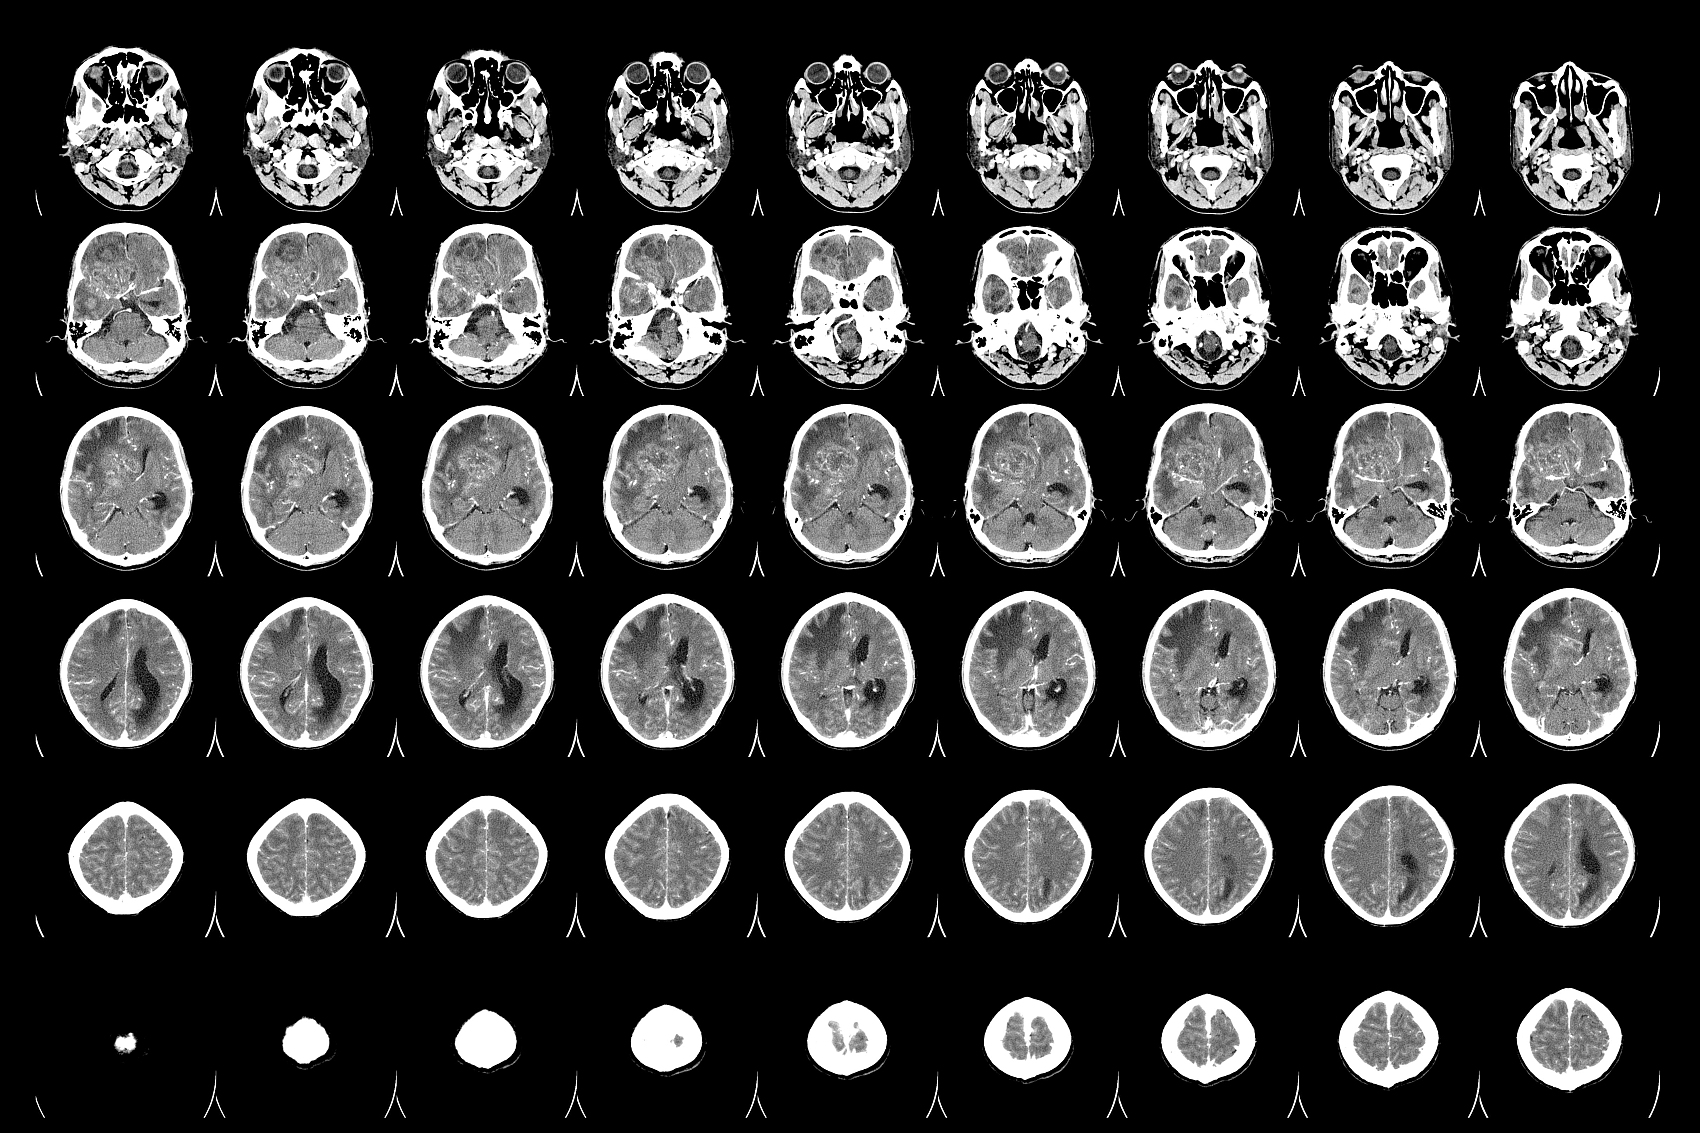

膠質(zhì)瘤的含義是什么,什么是膠質(zhì)瘤

膠質(zhì)瘤的癥狀,達(dá)州治療膠質(zhì)瘤去哪家腫瘤醫(yī)院-達(dá)州醫(yī)科腫瘤醫(yī)院膠質(zhì)瘤是一種常見的神經(jīng)系統(tǒng)腫瘤,它起源于大腦和脊髓的膠質(zhì)細(xì)胞...